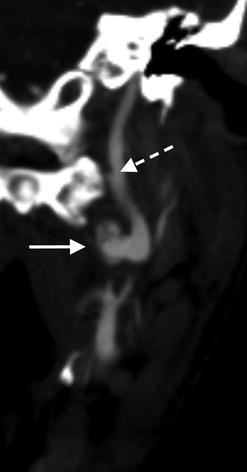

Axial CTA image through the neck in a 24-year-old male following blunt motor vehicle trauma shows a psuedoaneurysm (dashed arrow) arising from the medial aspect of the cervical left internal carotid artery (arrow)

Coronal CTA image reveals an intimal dissection flap (dashed arrow) distal to the site of pseudoaneurysm formation (arrow)